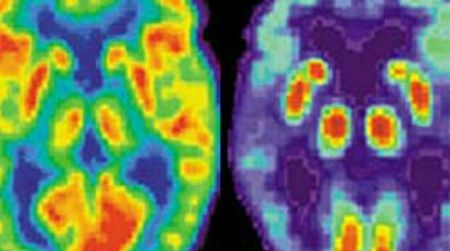

How Brains Make Money

A new breed of scientists says that if you want to understand why people make financial decisions, you need to see what’s going on inside their brains